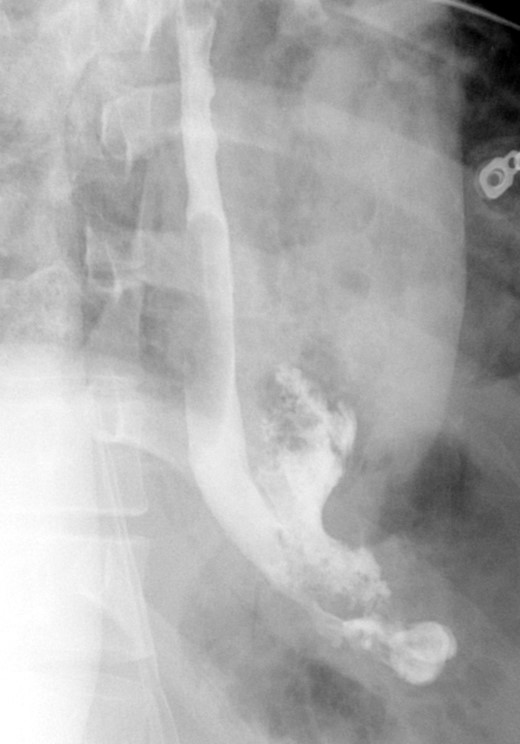

A computed tomographic scan revealed air and fluid surrounding the esophagus (Fig. 1). Esophagogram performed with water-soluble contrast media showed a distal esophageal perforation with a free leak into a large mediastinal cavity to the left of the esophagus (Fig. 2). The patient was triaged directly to the operation room. A left chest tube was placed with improvement in his oxygenation, and grossly murky fluid was drained. Esophagogastroduodenoscopy (EGD) was performed next and revealed a very small caliber esophagus with concentric ringed appearance. A tight stricture was noted in the mid-esophagus, which only allowed passage of a pediatric gastroscope. In the lower esophagus, a 2-cm tear with necrotic edges was visualized 3 cm above the gastroesophageal (GE) junction. With this diffusely strictured and very diseased appearance of the esophagus, the decision was made to proceed with stent placement and thoracoscopic drainage of the mediastinum rather than primary surgical repair via thoracotomy. A fully covered, 15 cm × 19 mm, EndoMAXX® esophageal stent was successfully placed covering the perforation site. Mediastinal washout and drainage was performed subsequently via left thoracoscopy. A postoperative esophagram showed no leak and the patient was started on a liquid diet that was tolerated well. His hospital stay was uneventful, and he was discharged on twice daily high-dose proton pump inhibitor (PPI) on post-operative Day 5. He was placed on a mechanical soft diet on discharge. Repeat upper GI study with water soluble contrast postoperatively showed no evidence extravasation. (Fig. 3)

Demonstrates narrow esophageal caliber and extensive distal left thoracic esophageal leak approximately 3 cm proximal to the GE junction.